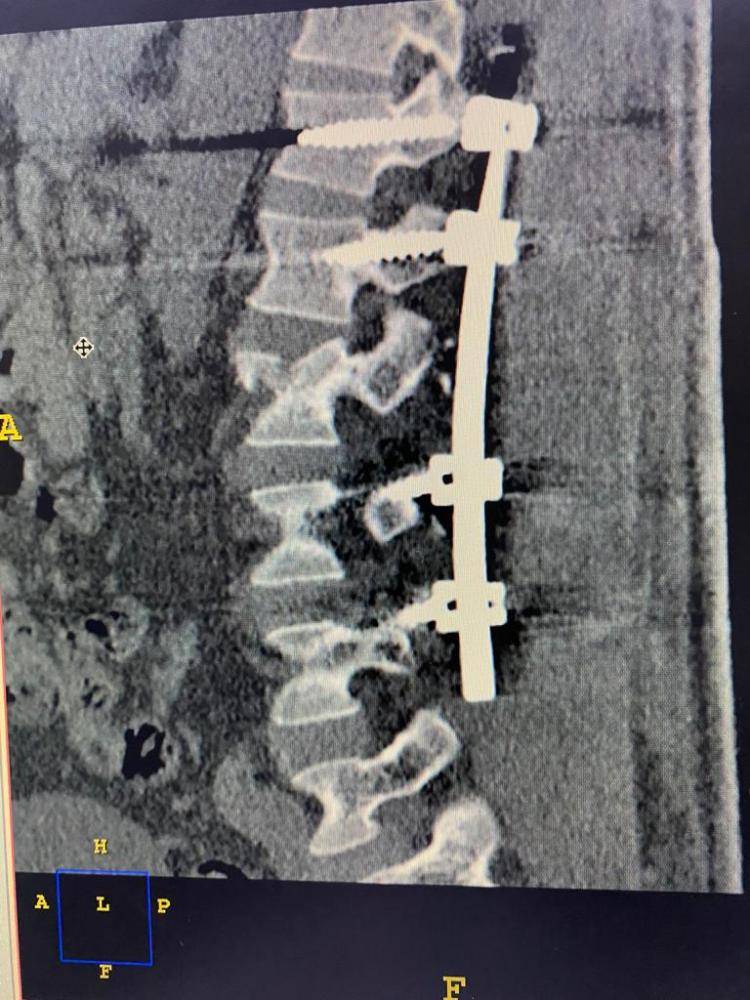

وفي ذات السياق، تم إجراء العملية الثانية لمواطن في العقد السادس كان يعاني من كسر في الفقرة القطنية الأولى الصدرية ضاغط على القناة الفقرية وغير مستقر، قام الفريق الطبي بتثبيت الفقرات الصدرية من الفقرة الثانية عشرة حتى الثالثة عشرة القطنية.

وفي حالة أخرى لمقيم في العقد الرابع كان يعاني من كسر في الفقرة الثانية عشرة الصدرية ضاغط على الحبل الشوكي والقناة الفقرية، قرر الفريق الطبي إجراء عملية تثبيت الفقرات من العاشرة الصدرية وحتى الثانية القطنية مع إزالة الضغط على القناة الفقرية الثانية عشرة. حيث تكللت جميع العمليات بالنجاح.